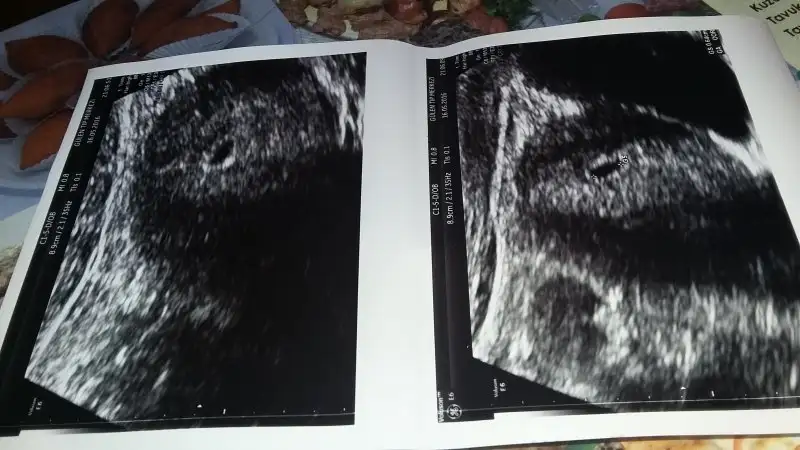

Geç döllenmedir sakin olBenimde 5+2 olmam lazimdi ama malesef 4+3 cikti kese cok duzgun dedi doktorum ama ben cok korkuyorum

Benimde 5+2 olmam lazimdi ama malesef 4+3 cikti kese cok duzgun dedi doktorum ama ben cok korkuyorum